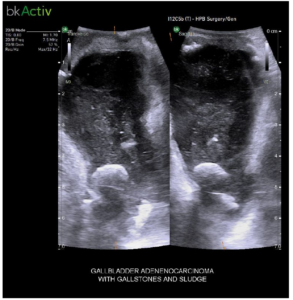

Gallbladder Adenocarcinoma with Gallstones and Sludge

iUS helps differentiate between sludge, stone, polyps, cysts, and tumors when determining if there is a presence of gallstones in the common bile duct.5.6